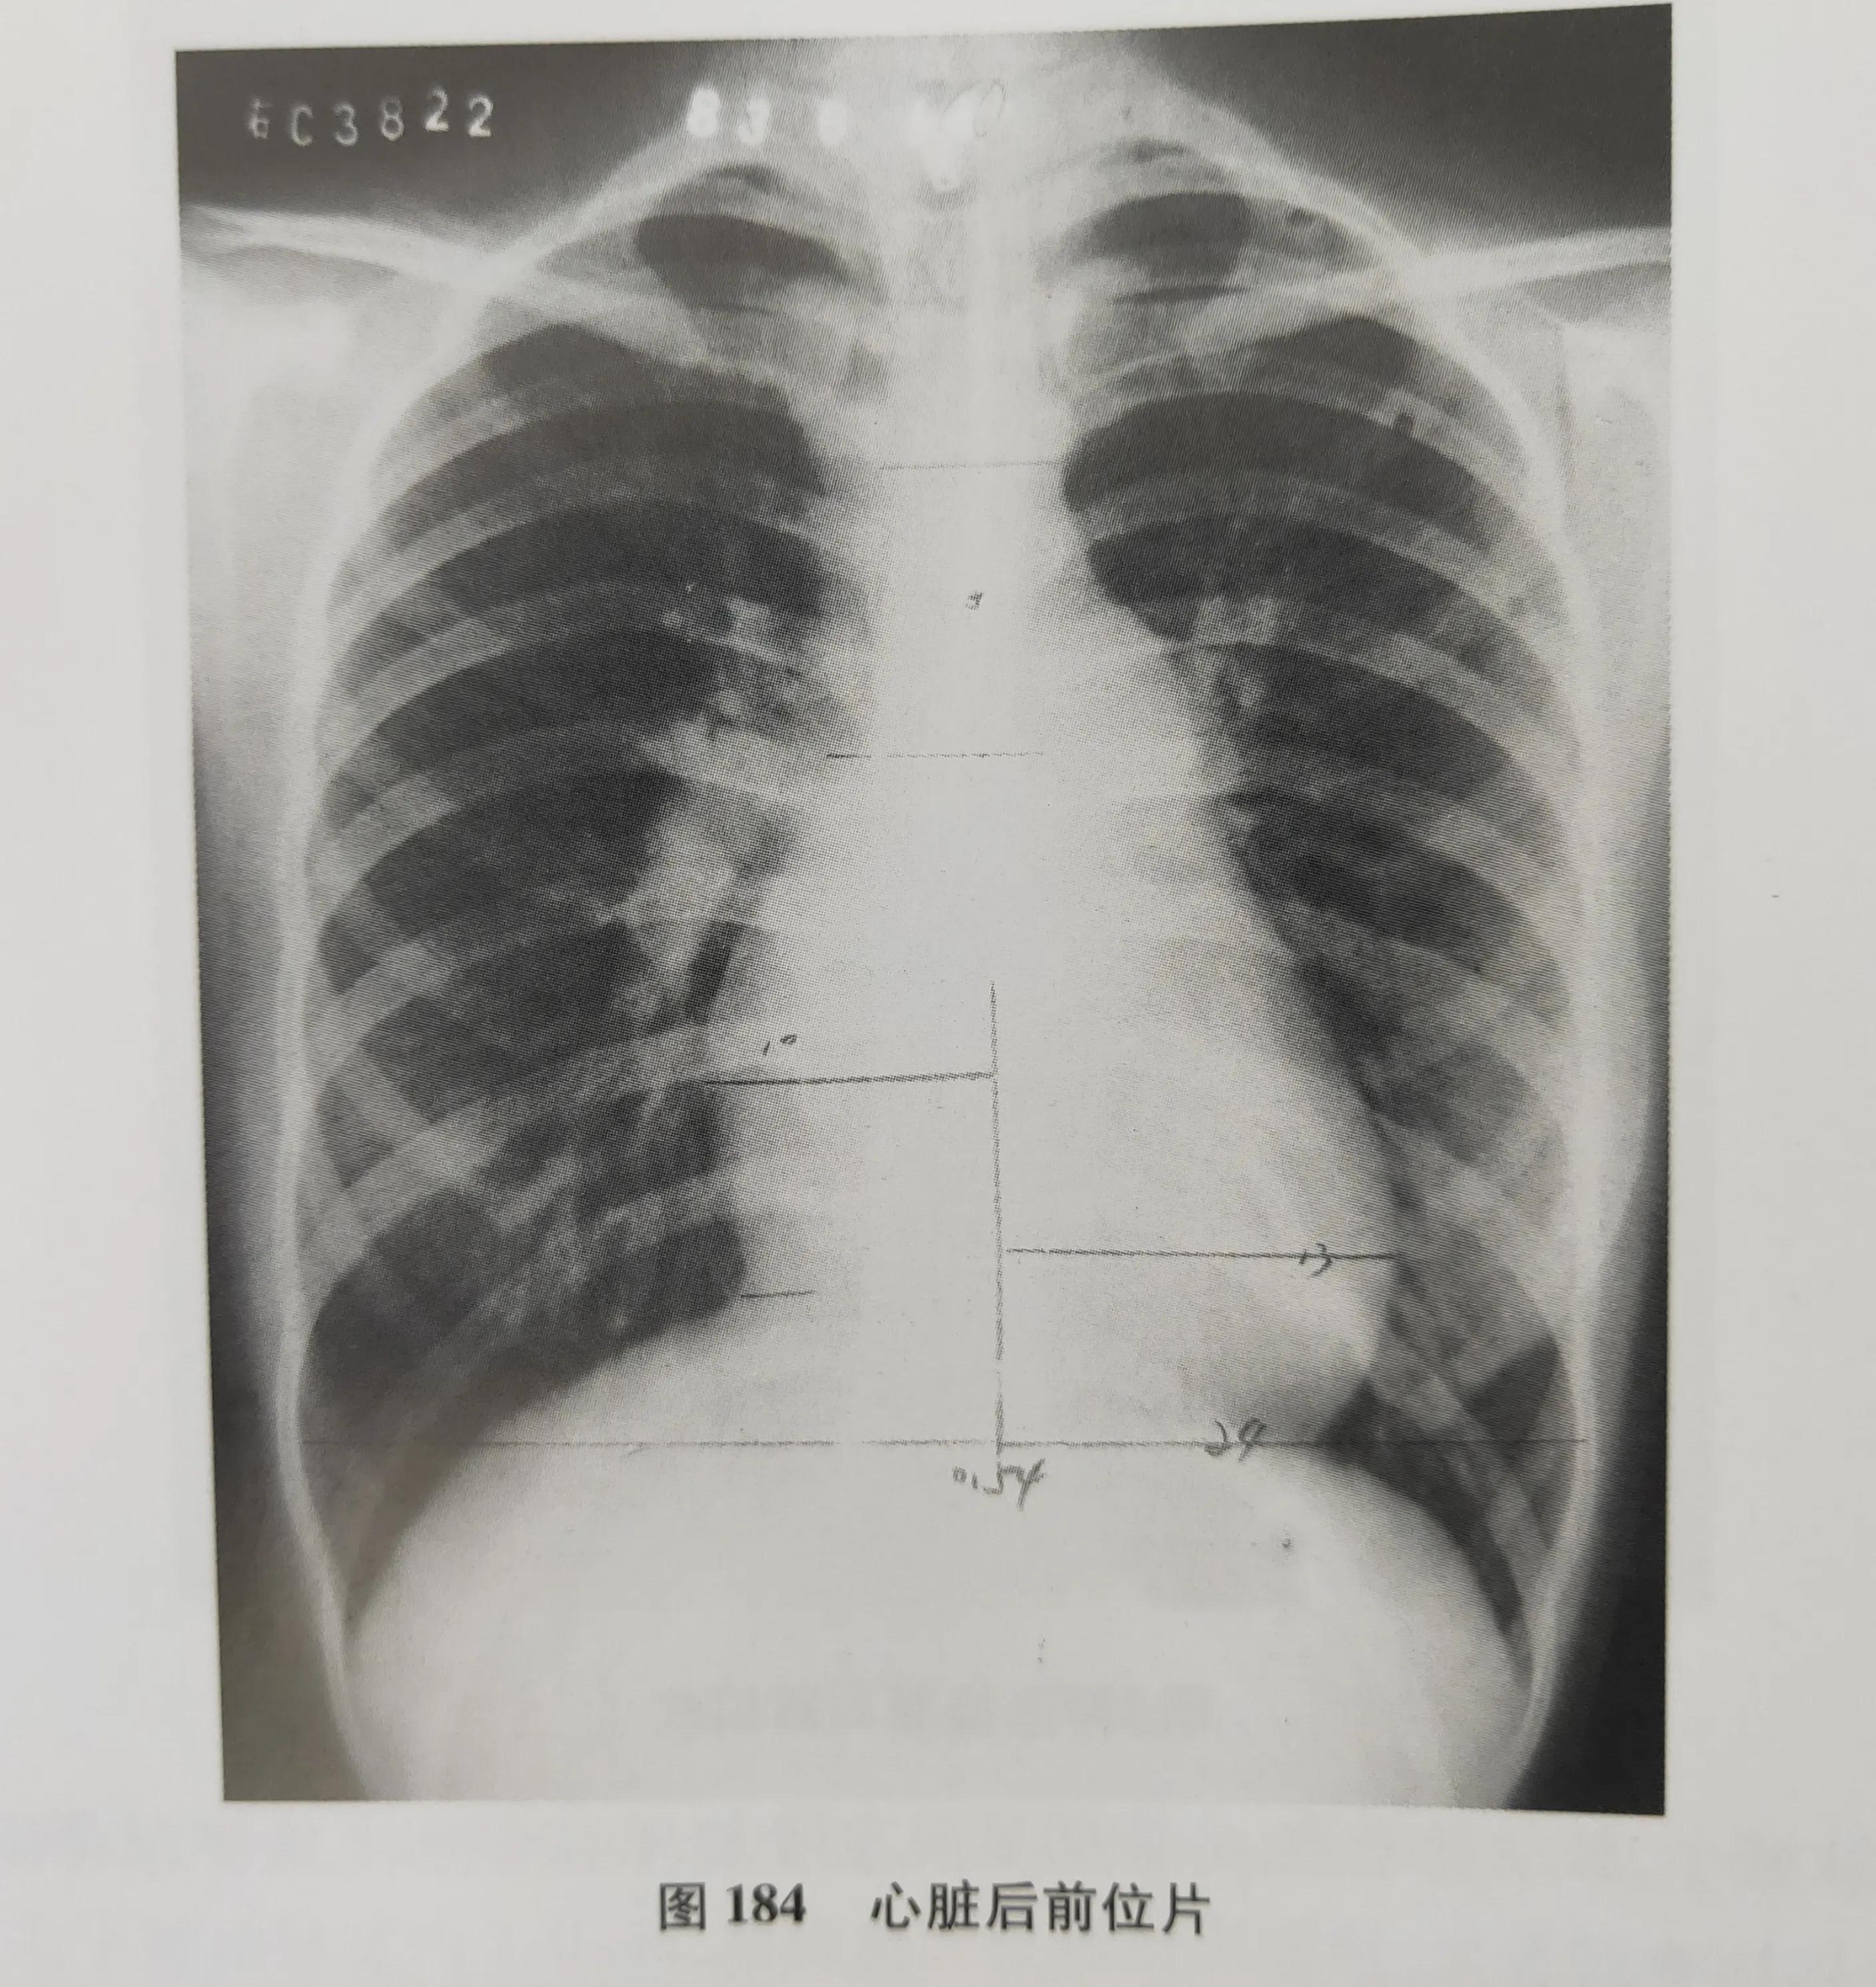

在X线片上呈现的黑白灰等差别,可做四种密度:我们在片子上看到的白色的,是高密度,就是我们的骨头或钙化灶,如股骨、颅骨。我们看到的灰白色的,是中等密度,是我们的软骨、肌肉、神经、实质器官、结缔组织及体液。我们在片子上还能看到灰黑色的,这个是较低密度,是我们的脂肪组织。最后X线片上看到的黑色,是低密度,是气体,比如拍的胸片,如果是一大片黑,那很有可能是气胸了。

但是也有例外,因为成像的基本条件与物体的密度、厚度有关,如肋骨的密度高,但是它薄;而心脏大血管虽说是软组织,是属于中等密度,但是它厚啊,因此在X线片上显示的结果就是心脏大血管要比肋骨的白。